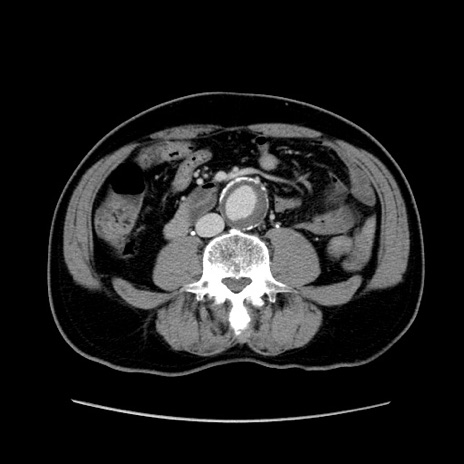

症例34(横断像)

【症例】60歳代 男性

【主訴】右鼠径部膨隆

【現病歴】1年程前より右鼠径部膨隆あり。自己にて還納可能だったため放置していた。3時間前より右鼠径部の脱出を認め、還納困難となり受診。

【既往歴】高血圧

【身体所見】右鼠径部に小児頭大の膨隆あり。弾性硬であり、用手還納は困難。左鼠径部にも膨隆を認める。脱出はなし。

【データ】WBC 15500、CRP 測定なし